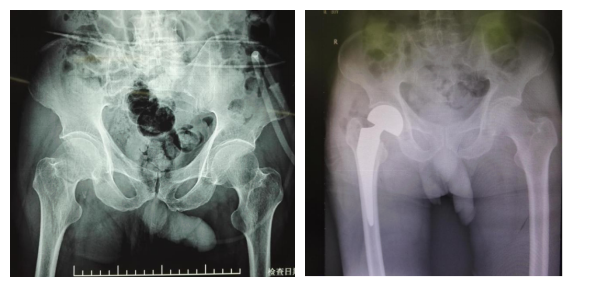

您的位置: 首页>科室导航>骨科>创伤骨科与手外科>科室新闻